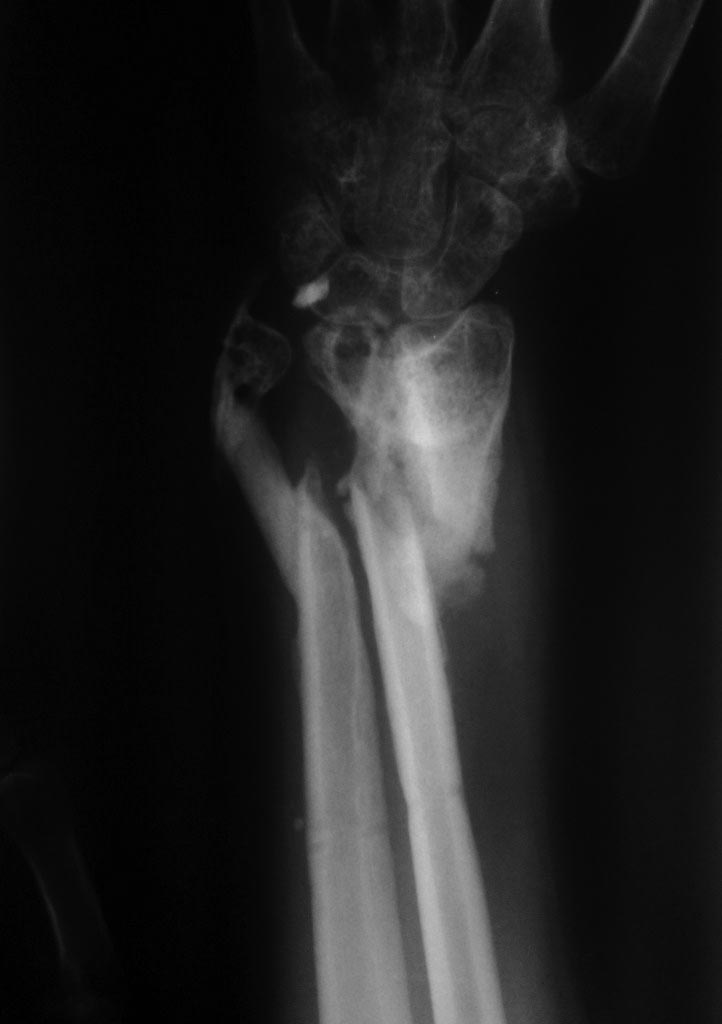

[Ortho] неправильно сросшийся перелом предплечья

Снимки досылаю. Спасибо